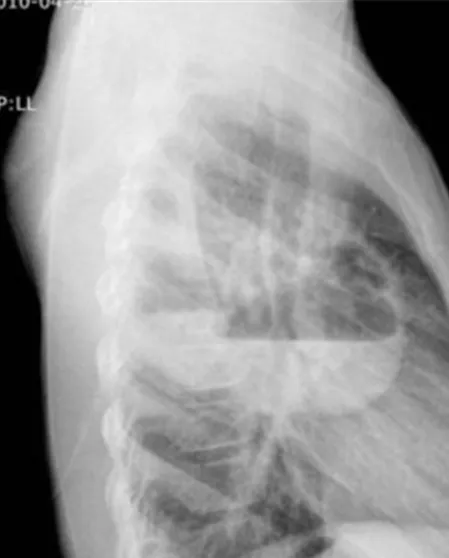

61세 남성이 지난 10일 동안 지속된 발열과 함께 불쾌한 냄새가 나는 화농성 객담을 호소하며 병원을 찾았다. 환자는 15년간 흡연한 이력이 있으며, 최근 3년 간 매일 소주 두 병을 섭취하는 등의 과음 습관이 있었다. 또한, 환자는 몇 주 전에 치주 질환으로 치과 치료를 받았다고 한다. 아래는 환자의 흉부 X선 사진 결과이다. 이 환자에게 가장 적절한 치료 방법은 무엇인가?

알콜중독과 치주염 병력으로, 혐기균의 aspiration risk 높은 환자다. 가슴 X선에서 air-fluid level이 보이는 thick walled cavity가 보이므로 lung abscess를 의심할 수 있다. 또한 불쾌한 냄새의 화농성 객담은 "Putrid lung abscess"를 시사하는 소견이다.